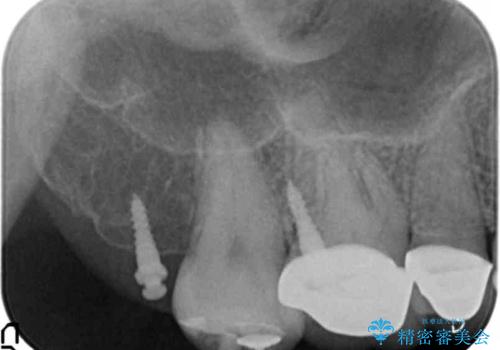

伸びてしまった奥歯、咬合平面を揃えたインプラント治療

- 右下の歯を虫歯で抜去し、インプラント治療を希望され来院されました。

インプラントを埋入するのに十分な骨は存在しますが、放置した間に上の歯が伸びてきてしまいクラウンのスペース不足な状態です。

通常このような場合、神経を除去し歯を短くしたのちインプラント治療を行いますが、今回はマイクロインプラントを用いて歯を歯ぐきの方向へ沈めたのち神経を温存する形でインプラント補綴を行いました。

伸びてしまった上の奥歯を、神経もとらず、クラウンにもせず治療することができ、喜んでいただくことができました。